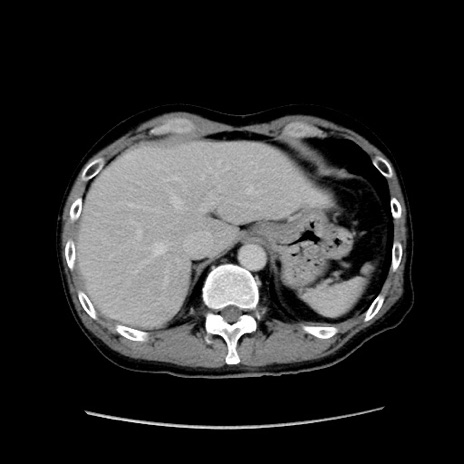

症例37(横断像)

【症例】40歳代 男性

【主訴】腹痛

【現病歴】4時間ほど前に電車に乗車中に臍部上より腹痛出現。徐々に増悪し起立困難となり、救急外来受診。生ものは数日食べていない。今朝お雑煮を食べた。

【身体所見】BT 36.8℃、BP 117/84mmHg、HR 91/min、SpO2 97%、苦悶様、腹部:臍上部広範囲圧痛あり、反跳痛±

【データ】WBC 8100、CRP 0.03